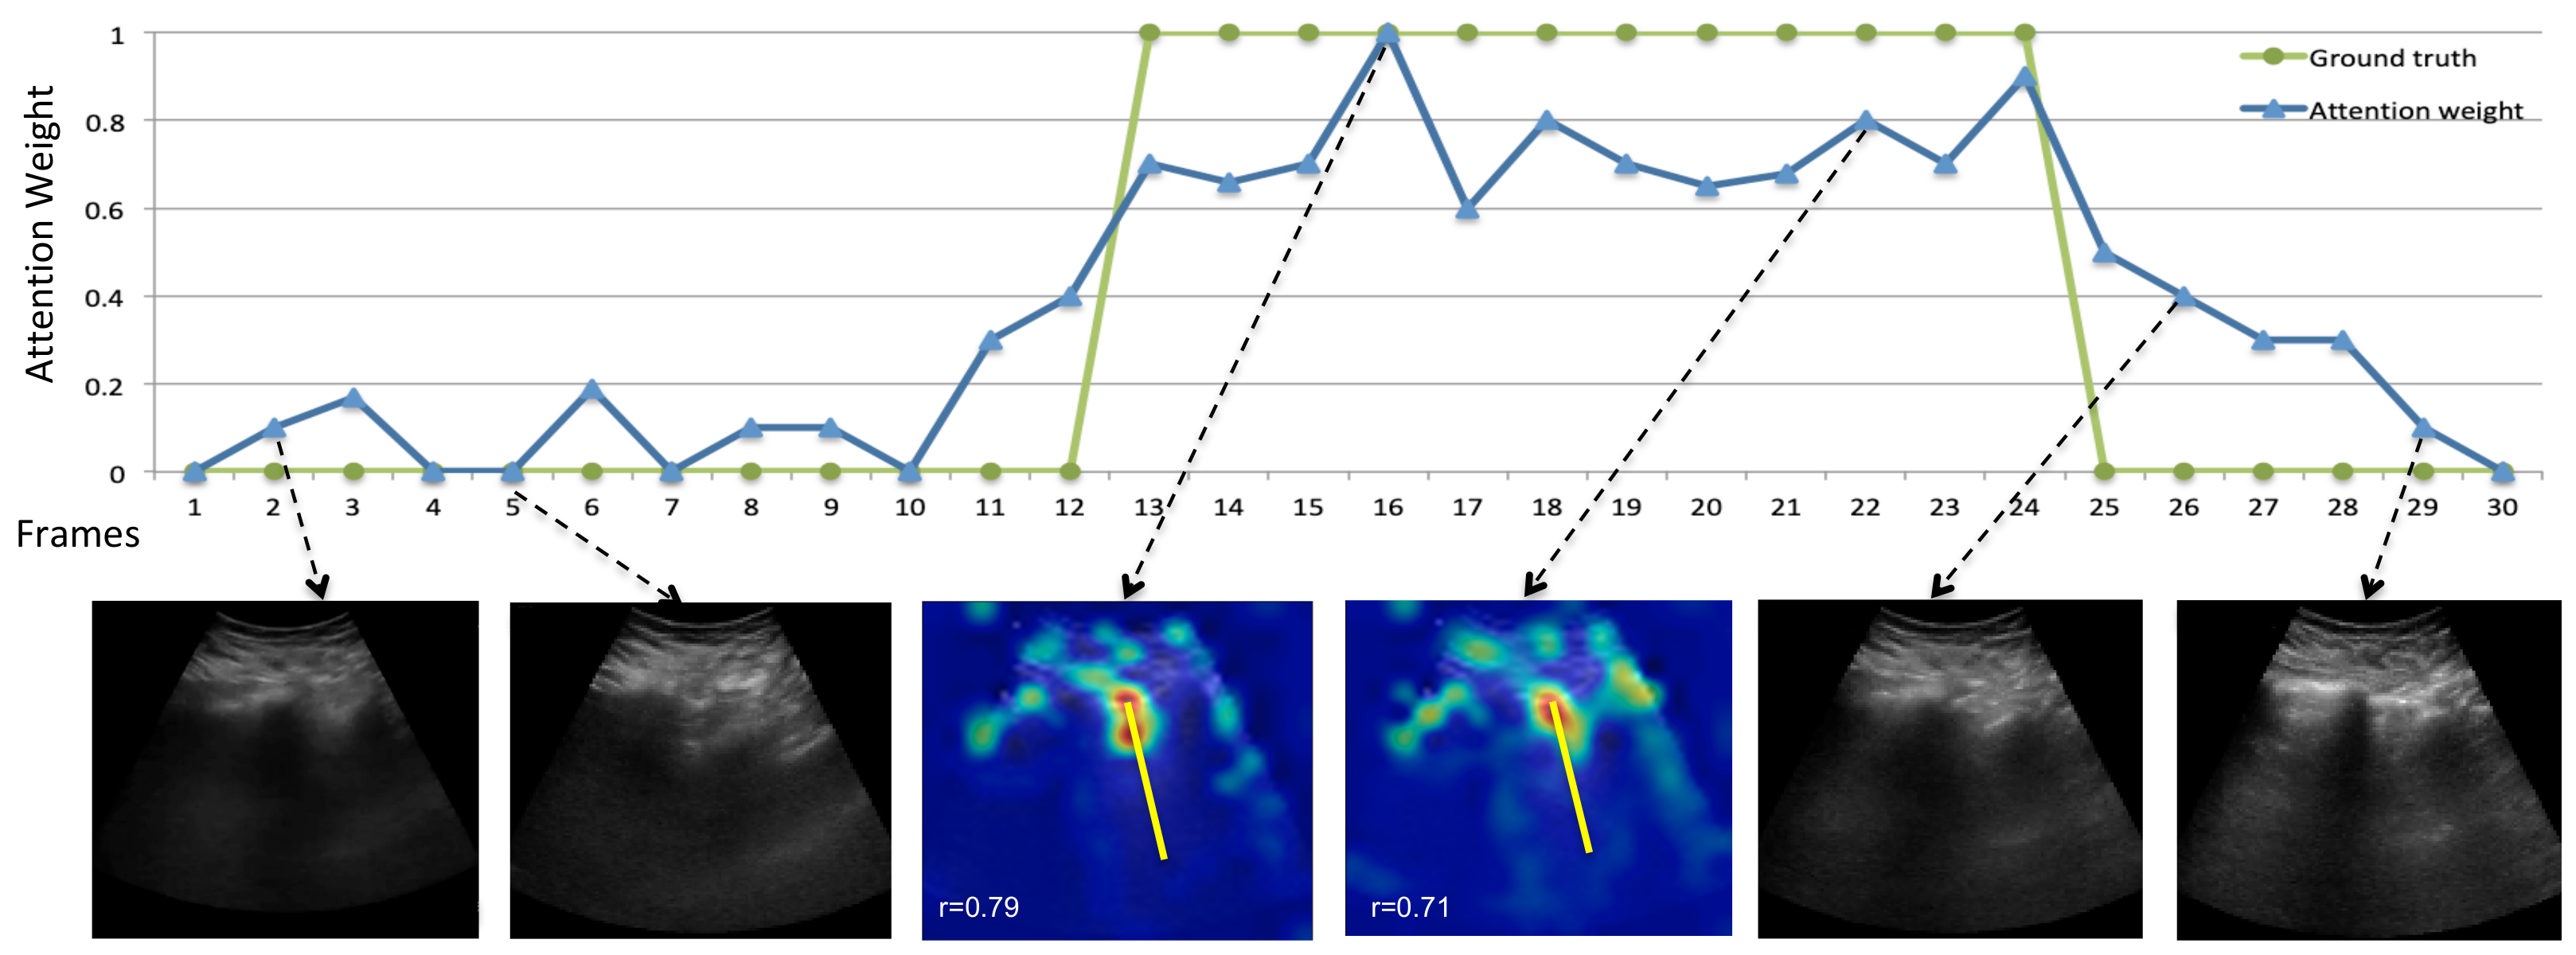

5.3. Temporal B-Line Localization